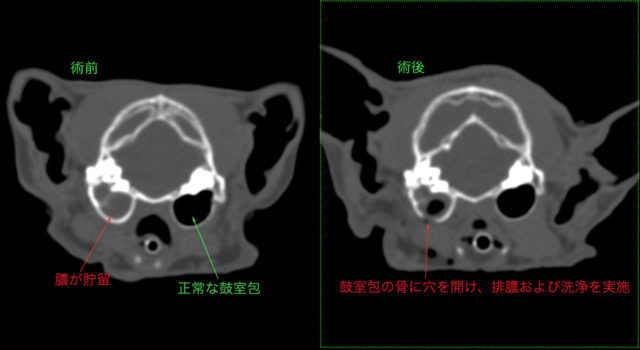

貯留液の採取および洗浄のために鼓室包切開術を実施

膿が採取されたため、薬剤感受性試験を行い抗生剤による治療を行い、その後症状良化

術前後のCT画像